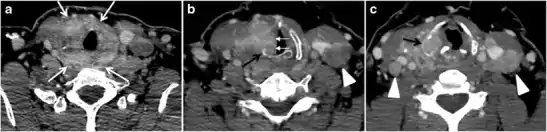

Fig. 5. A poorly differentiated invasive left thyroid mass in a 58-year-old female patient. a Sagittal greyscale neck ultrasound shows a large hypoechoic lesion with macro-calcification and micro-calcification. b Sagittal colour Doppler ultrasound shows left internal jugular vein filling defect with detected internal vascularity suggestive of tumour thrombus. c Enhanced axial and coronal CT scans of the neck show heterogeneously enhancing large lesion replacing the left thyroid lobe and extending to the isthmus and the medial aspect of the right thyroid lobe (white arrow). The mass and the conglomerate lymph nodes measure 12.5 × 7 × 5.8 cm (white arrows). d, e Axial enhanced CT scans show enlarged left cervical nodes (white arrow) and left internal jugular vein (IJV) thrombus (black arrows). Note the IJV distention and central enhancing portion in the upper cut (black arrow in e) concerning the tumour thrombus. f, g Enhanced axial CT scan of the upper chest demonstrate a mass extension into the retrosternal area, left tracheoesophageal groove, and posterior to the trachea (white arrows in f). There are multiple bilateral pulmonary nodules (white arrows in g).[1]